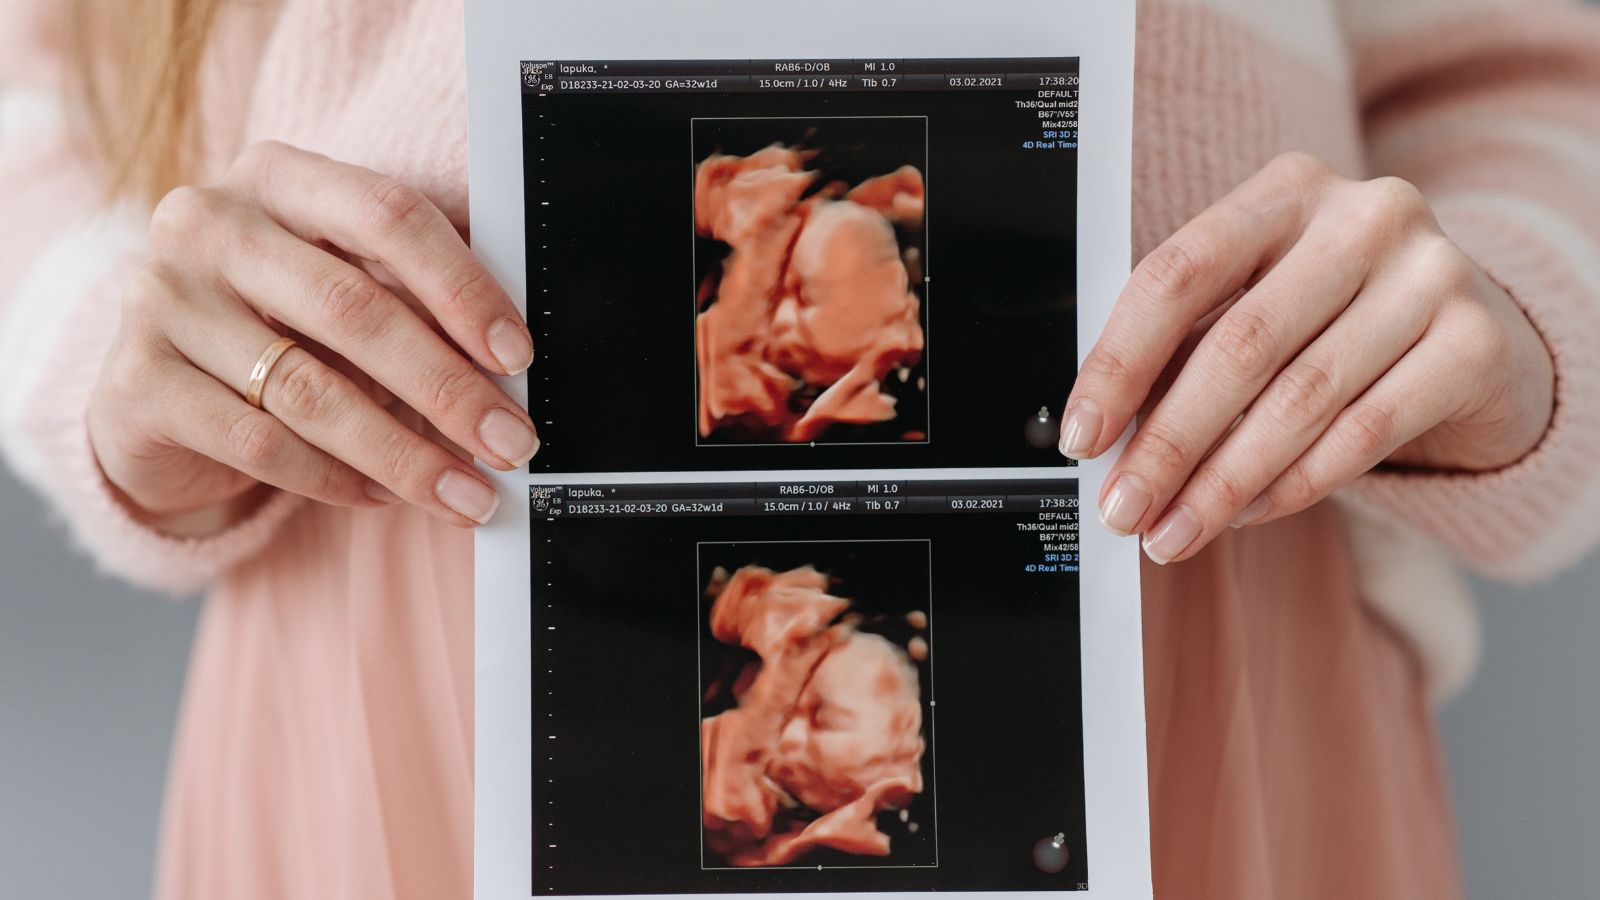

Siêu âm thai định kỳ

Siêu âm là phương pháp tốt nhất giúp phát hiện sớm tình trạng giãn quai ruột ở thai nhi. Thông qua siêu âm, bác sĩ có thể xác định mức độ giãn quai ruột và theo dõi sự phát triển của hệ tiêu hóa của thai nhi qua từng giai đoạn. Mẹ bầu nên thực hiện các lần siêu âm thai định kỳ theo chỉ dẫn của bác sĩ để kịp thời phát hiện bất kỳ vấn đề nào.